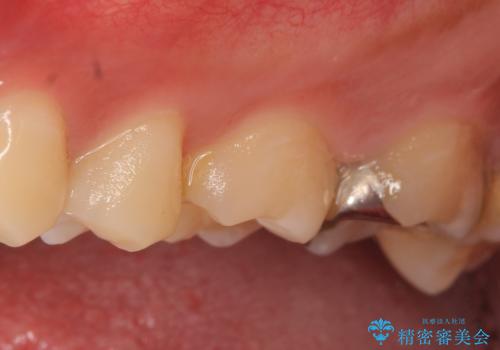

左上5、6、7番目の歯に虫歯を認めたため、左上5、7はセラミックインレーによる修復を行いました。

当院のセラミックインレーはemaxという強度と審美性に優れた材料を使用しています。

またプレス方式でインレーを製作しているため、削り出しで製作するCADCAMより優れた適合性も持ち合わせており、虫歯が再発しにくい修復物です。